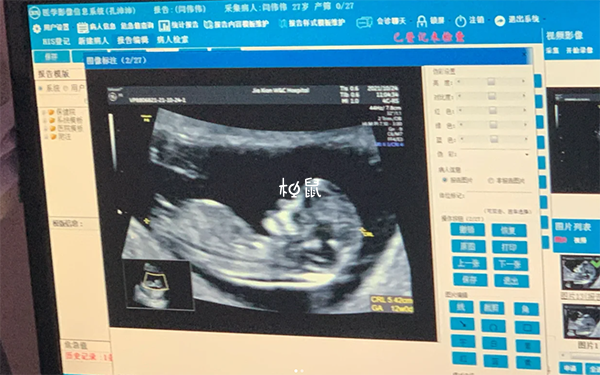

懷孕12周做nt是測量胎兒頸項透明層厚度,可用於判斷胎兒的生長情況,篩查由於染色體異常導致的嚴重胎兒畸形,胎停也就是指妊娠早期由於某種原因導致的胚胎髮育停止,引起胎兒死亡,多發生在妊娠12周以內,屬於婦產科常見的疾病,如果在做nt時發現胎停育的話,需要及時清宮,以免出現不良後果。

懷孕期間要選擇合適的時間進行各項產檢,不僅需要進行nt檢查,同時還需進行唐氏篩查和定期的超聲檢查,監測胎兒的生長髮育情況,如果檢查發現胎停,也不必過於焦慮,調整好心態,積極配合醫生進行相應染色體檢查,明確胎停育的原因,為下一次懷孕做準備。